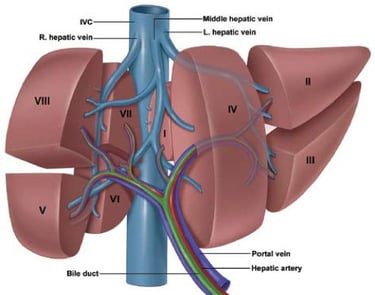

Cirurgia: A cirurgia é uma das principais opções de tratamento para o câncer de fígado, especialmente quando o tumor é ressecável.

Ressecção Hepática: Remoção da parte do fígado onde o tumor está localizado. Pode ser uma opção curativa para tumores pequenos e em estágio inicial.

Transplante de Fígado: Substituição do fígado doente por um fígado saudável de um doador. Indicado para pacientes com doença hepática em estágio inicial e cirrose avançada.

Ressecção Hepática Metastática: A remoção cirúrgica das áreas do fígado afetadas por metástases colorretais. Pode ser realizada em pacientes com um número limitado de metástases e função hepática adequada.

A Importância do Tratamento Cirúrgico

A cirurgia oferece a melhor chance de cura para pacientes com câncer de fígado em estágio inicial e para aqueles com metástases hepáticas de câncer colorretal ressecáveis. A remoção completa do tumor ou das metástases pode levar à remissão da doença e melhorar significativamente a qualidade de vida do paciente. Mesmo em casos avançados, a cirurgia pode ajudar a controlar os sintomas e prolongar a sobrevivência.